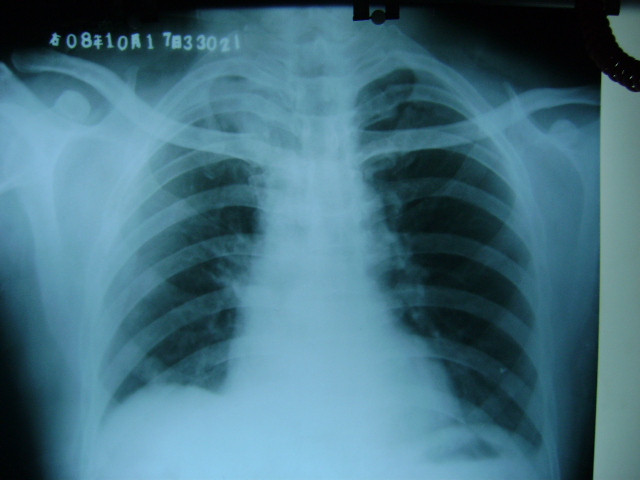

标题: CT16197:新手求教,M,42y,外伤入院,略感气紧,余无不适 [打印本页]

标题: CT16197:新手求教,M,42y,外伤入院,略感气紧,余无不适

肋骨骨折,肺挫伤,胸腔积液,不张?

肋骨骨折,右肺挫裂伤,右侧胸腔积液,没有气胸很奇怪啊

肋骨骨折,肺挫伤,胸腔积液,

肋骨骨折,肺挫伤,胸腔积液。

肋骨骨折,肺挫伤,胸腔积液,左肺代偿性气肿.

肋骨骨折,肺挫伤,胸腔积血.

肋骨骨折,肺挫伤,胸腔积血

肋骨骨折,胸腔积液并部分包裹,创伤性湿肺.

右侧肋骨骨折,右肺挫伤,右侧胸腔积液(血)。

支持肋骨骨折,肺挫伤,胸腔积血.

肋骨骨折,肺挫伤,双侧胸腔积血.